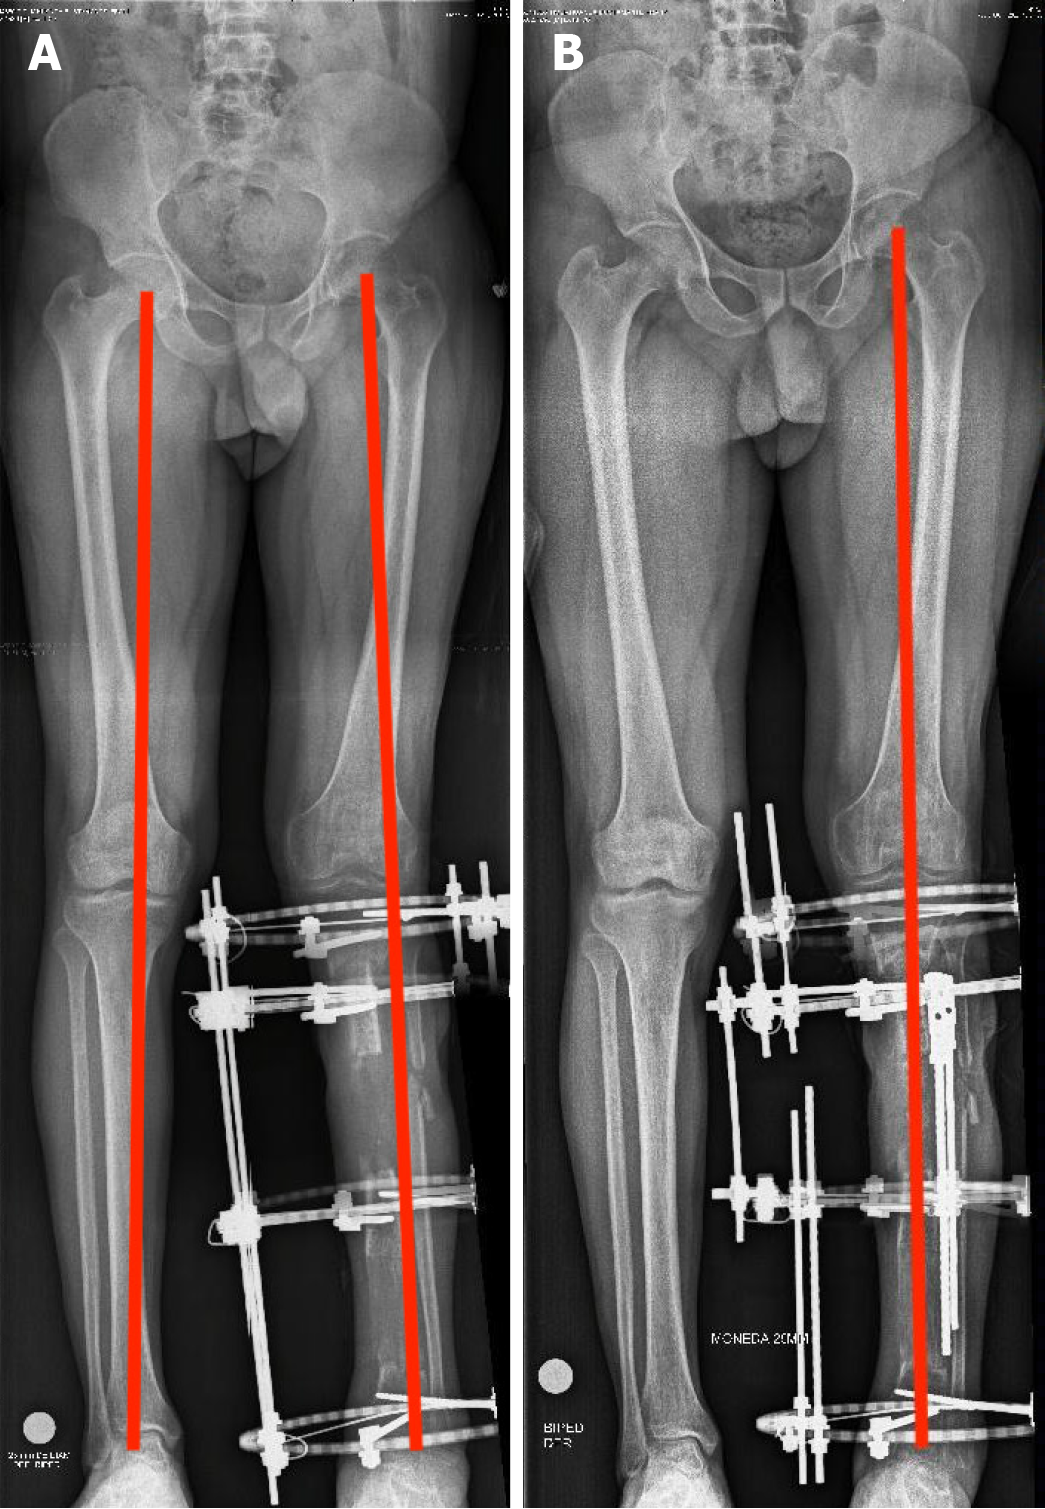

A 30-year-old male with a history of open tibial shaft fractures complicated by infections presented with a segmental bone defect of 13 cm and a soft-tissue defect measuring 10 cm × 15 cm. The patient was treated with radical debridement, anterolateral thigh free flap coverage, and trifocal bone transport with a circular Ilizarov fixator. A secondary correction of a mechanical axis deformity and sub

A 30-year-old male presented with an infection, a bone defect measuring 13 cm, and a soft-tissue defect measuring 10 cm × 15 cm in the anteromedial leg (Figures 1 and 2).

The patient underwent radical debridement of nonviable bone and soft tissue (Figure 3), and he received negative pressure therapy. An anterolateral thigh free flap was used for the reconstruction of the soft-tissue defect. An 8-week course of antibiotic therapy was administered, consisting of intravenous cefazolin (1 g every 8 hours) combined with gentamicin (80 mg every 8 hours) for the first 5 weeks, followed by cefazolin (500 mg every 6 hours) for an additional 3 weeks. Trifocal bone transport was performed with a circular Ilizarov fixator (Figures 4 and 5). The axis deformity was corrected simultaneously (Figure 6). Locking compression plates were applied to protect the bone regeneration after removal of the external fixation (Figure 7).